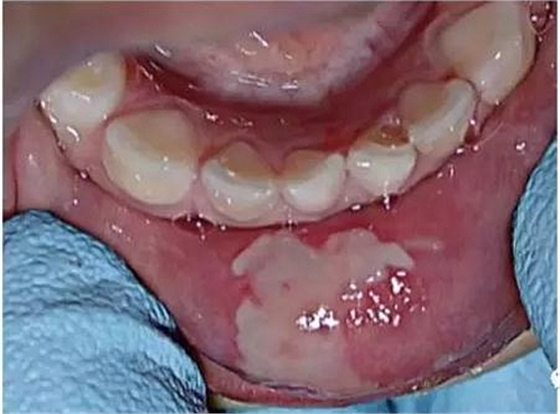

由于使用的麻醉劑,患兒將嘴唇咬傷

表麻下牙齦增生的激光切除即可效果